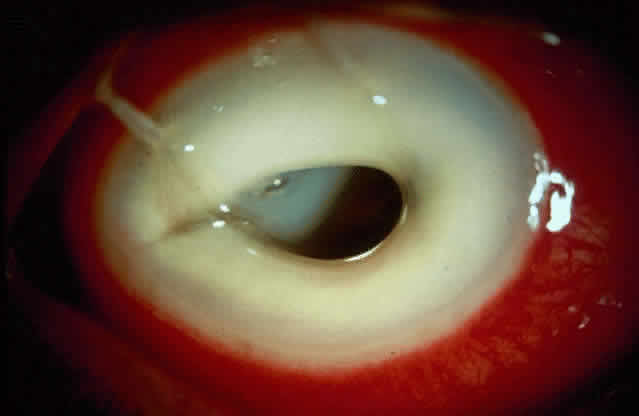

Bacterial corneal infections are caused by a wide variety of organisms. Pneumococcus seems to be the most common causative organism (Fig. 2); however, staphylococcal, pseudomonal, and gonococcal infections frequently are encountered.3 This may be related to chronic dacryocystitis.5

Fig. 2. Photograph demonstrating a pneumococcal corneal ulcer.